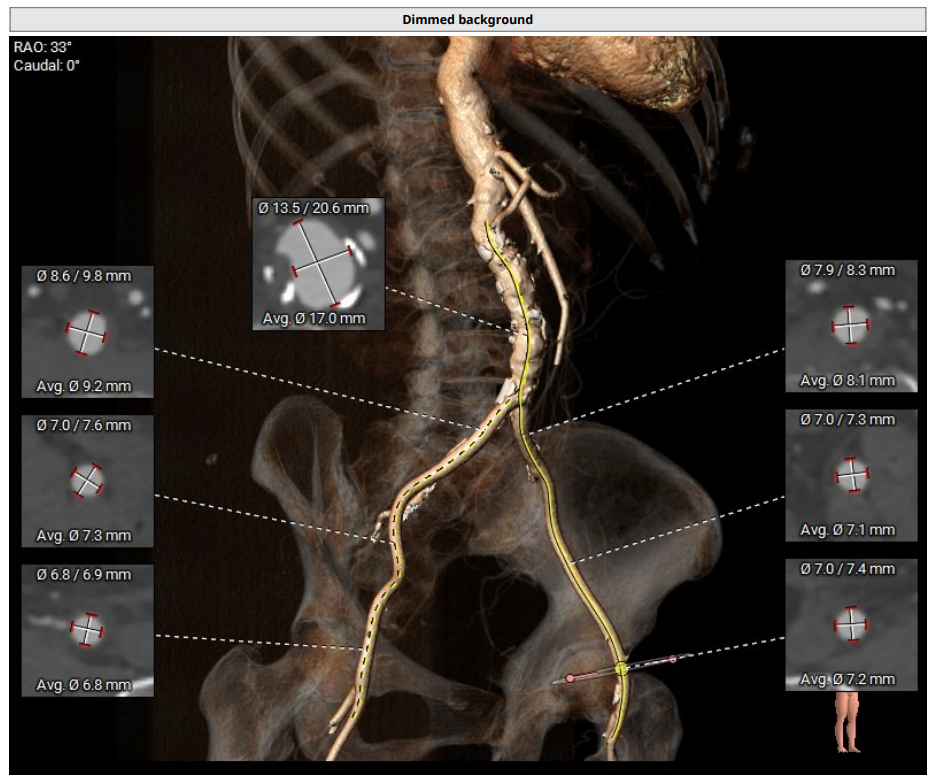

CT分析

TYPE0型二叶瓣,瓣叶增厚,重度钙化,左冠开口高度约18.5mm,右冠开口高度约19mm,法式窦结构大,STJ高度约25.4mm、直径约42.2mm,升主动脉增宽,最宽处约56 mm,心脏角度约60°,左室大。

主动脉根部解剖及入路分析